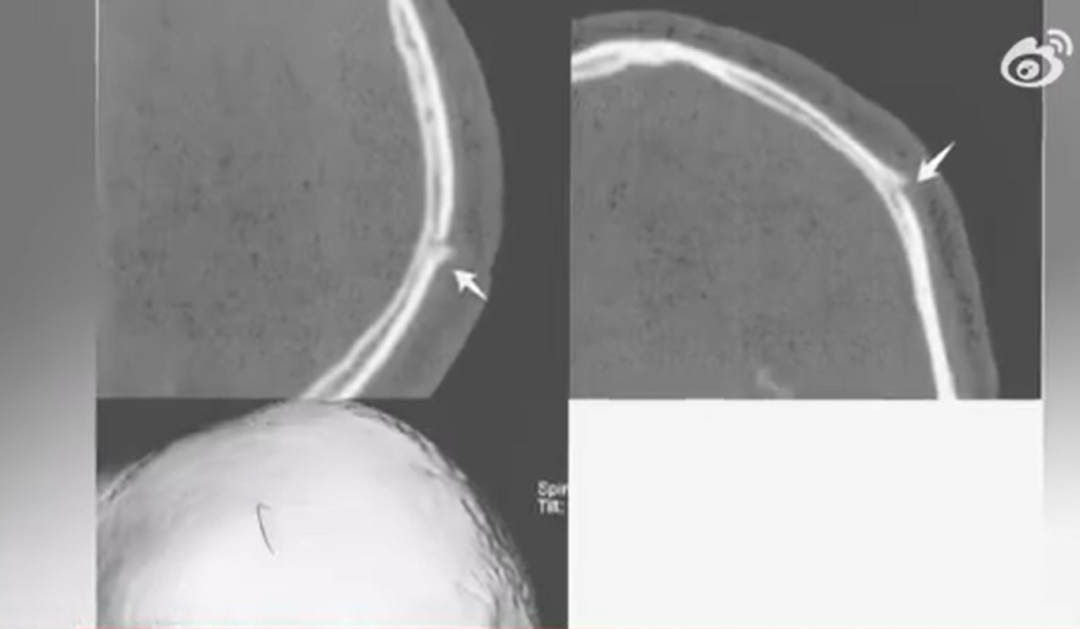

经鉴定,康某头部左顶骨骨折,构成轻伤二级;徐某头颈部、手部、腿部等多处挫伤,构成轻微伤。同年4月,公安机关以徐某涉嫌故意伤害罪提请批准逮捕。